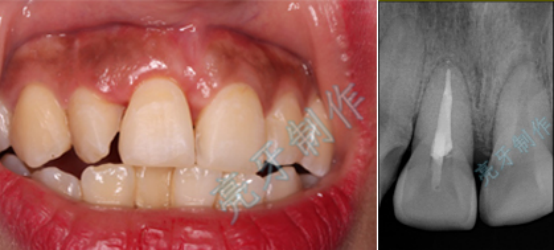

病例四:右侧前牙牙齿嵌入牙槽骨,无法咬合,治疗后,恢复功能和外形。